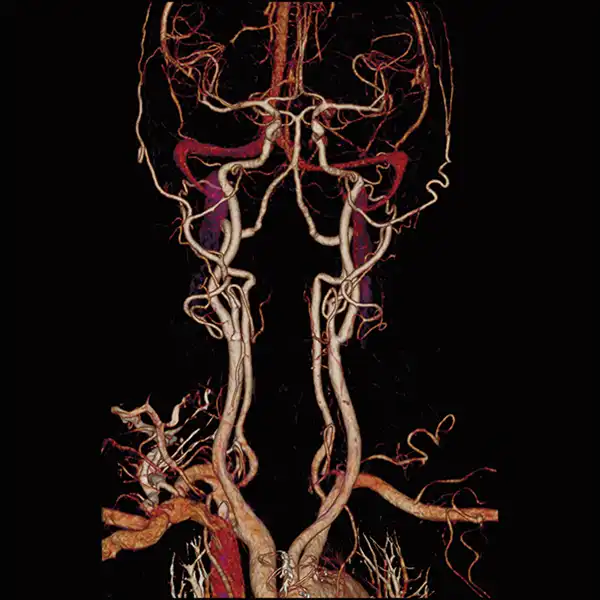

Angiography SURESubtraction CT* true subtraction of bone and calcium.

GENESIS Edition’s 16 cm wide area detector signicantly improves your ability to obtain high-quality images for routine and advanced studies. One rotation is all it takes to acquire a whole heart, a neonatal chest, a foot or an ankle exam – in a fraction of a second with less dose and great z-axis uniformity.